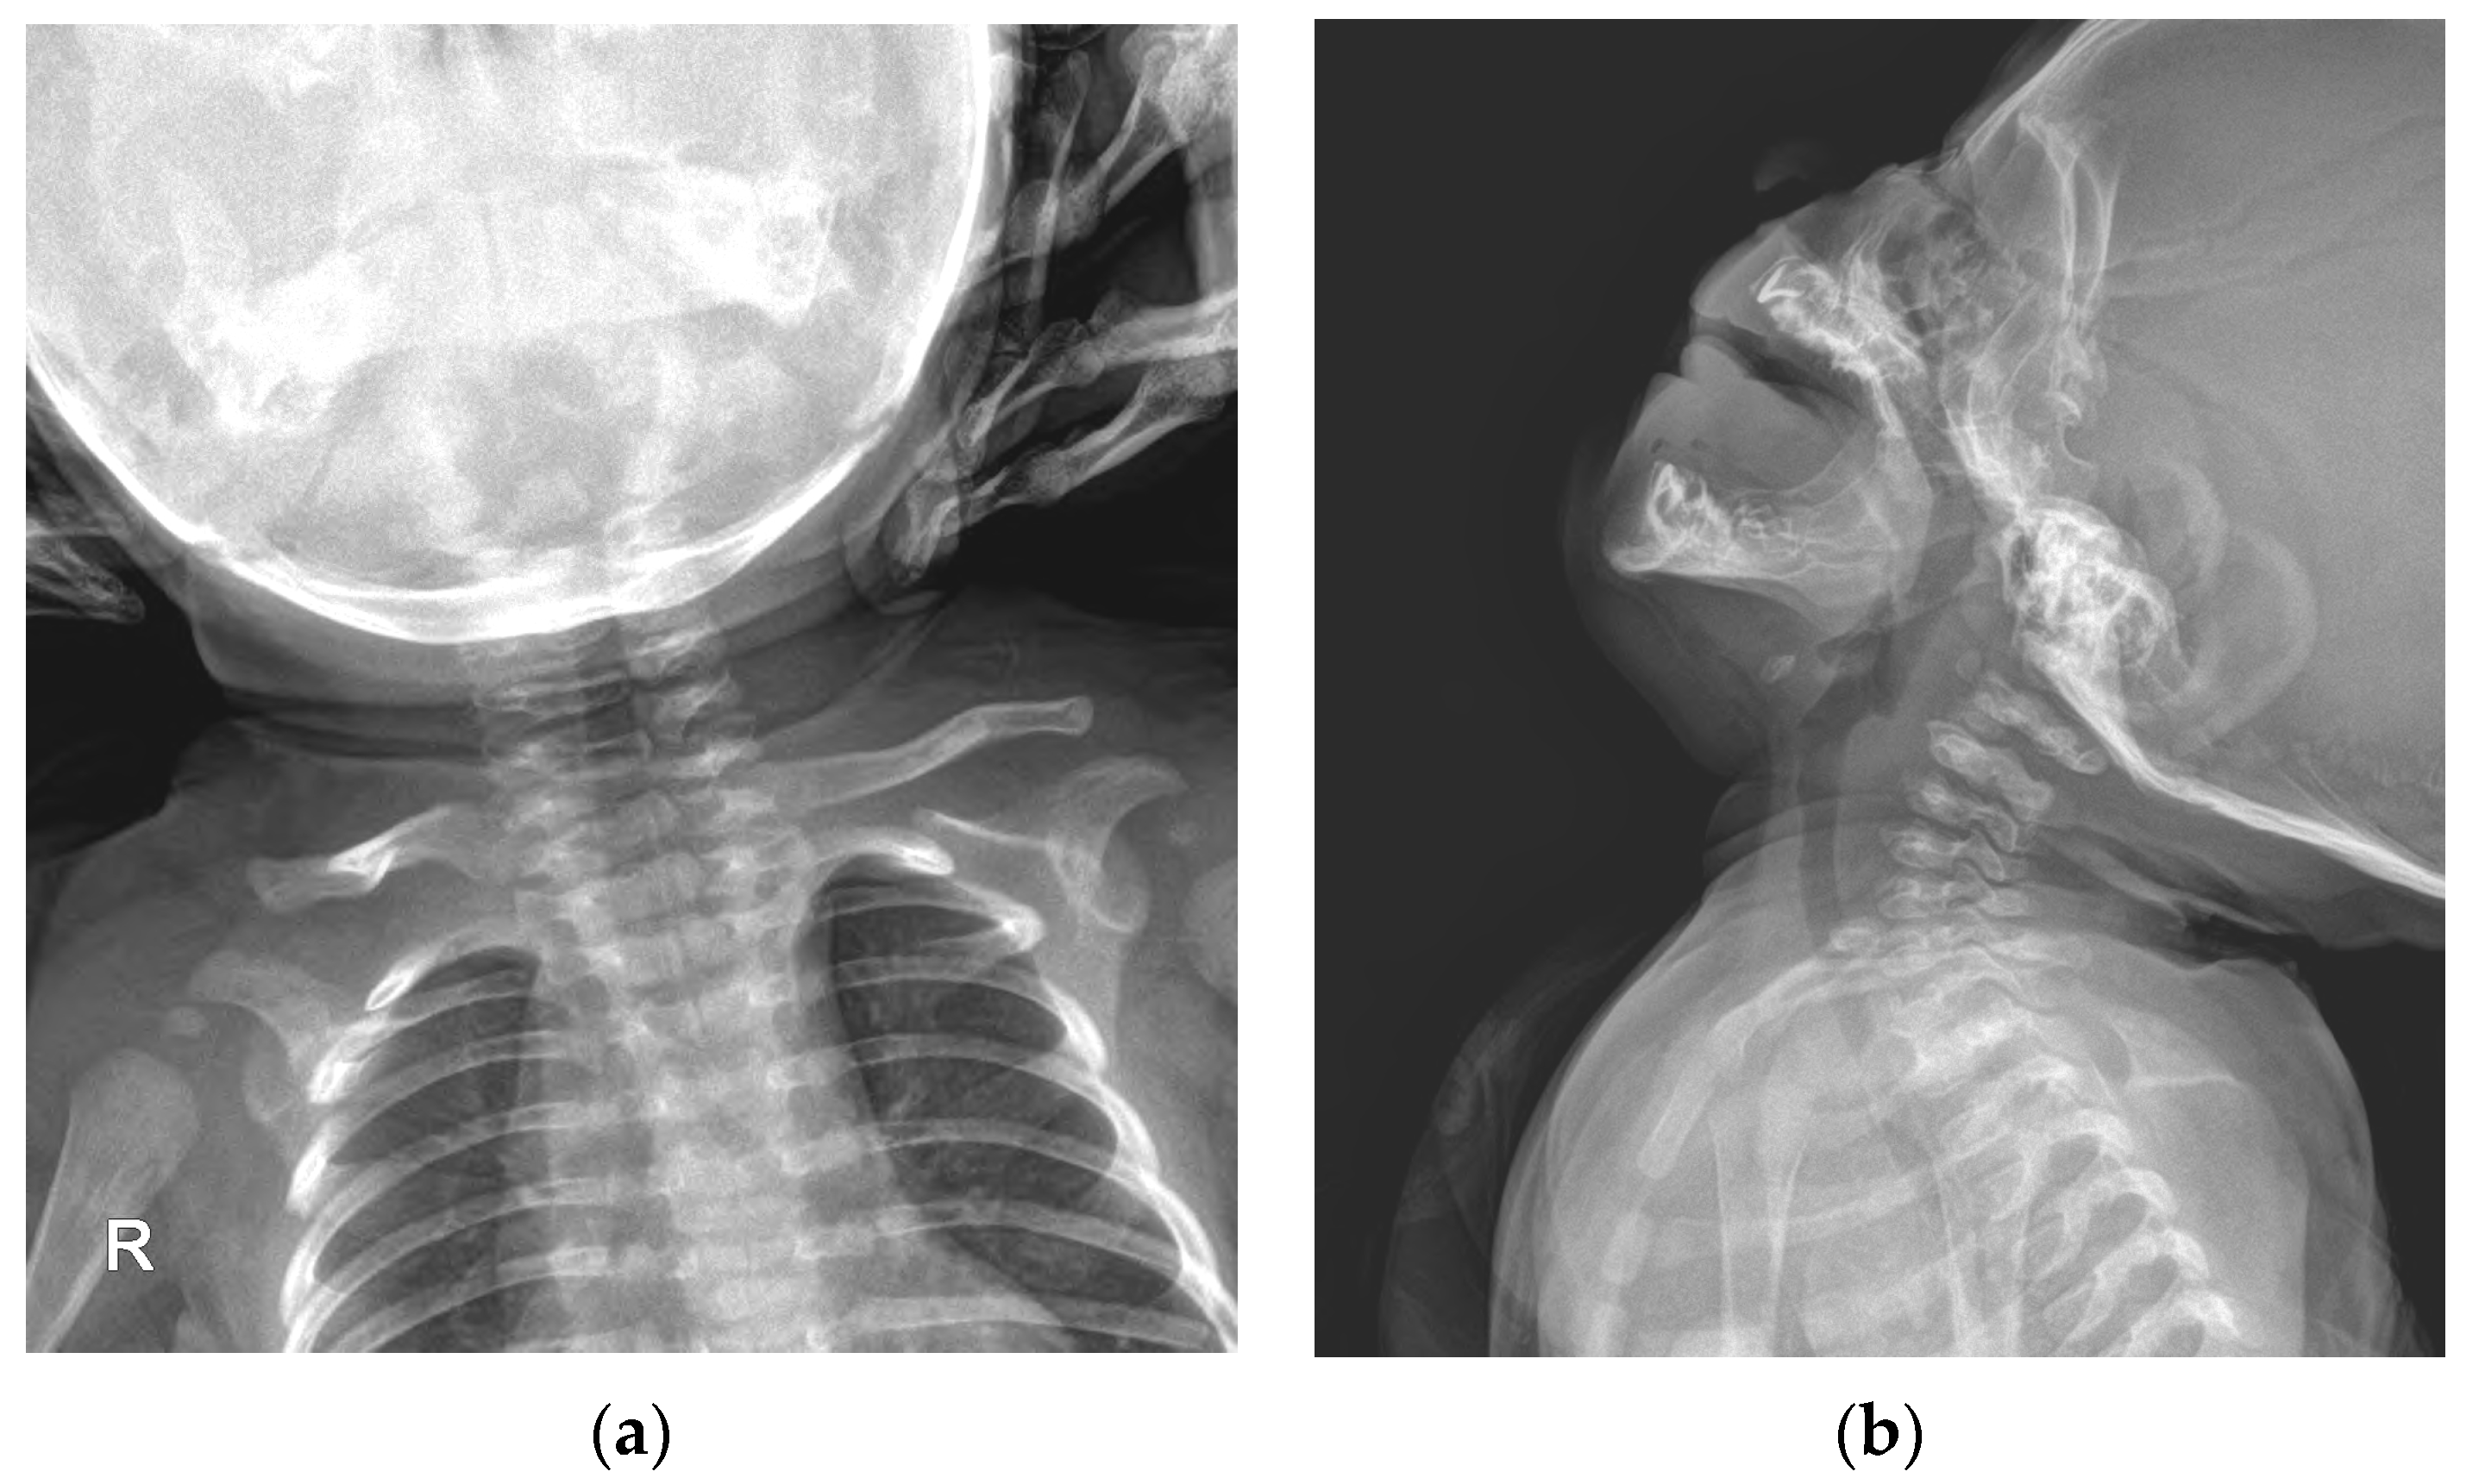

Ultrasound is the imaging modality of choice for radiographic evaluation of congenital muscular torticollis [8]. On ultrasound images, the SCM muscle appears as a relatively hypoechoic mass with echogenic lines; however, in cases of congenital muscular torticollis, the thickened SCM muscle mass can affect the size and signal intensity of the muscle. In conditions of congenital muscular torticollis, the affected SCM muscle looks thicker than the normal contralateral side, and the signal intensity of the muscle tends to be more hyperechogenic [8]. Neck ultrasonography exhibited asymmetric thickening of the right SCM muscle with hyperechogenicity (Figure 2). The thickness values of the SCM muscle at the right and left mid-levels were 12.9 and 4.7 mm, respectively, while the thickness values at the clavicular insertion point on the right and left sides were 10.9 and 2.1 mm. At the sternal insertion point, the right- and left-side thickness values were both 2.5 mm, and the baby exhibited prominent right-side muscular torticollis with fibromatosis coli.

Although idiopathic muscular torticollis was prominent, it can be viewed as a secondary change due to ipsilateral hemihypertrophy. According to a previous study by Hwang et al. [11], the average thickest part of the unaffected SCM muscle was 5.9 ± 1.1 mm, no more than 20% greater than that of the unaffected side. In this patient, the thickness values of the unaffected and affected sides were 4.7 and 12.9 mm, respectively. This discrepancy suggests that the SCM muscle was affected by ipsilateral hemihypertrophy.

Figure 2. Neck ultrasonography of the SCM muscle: (a) Thickness of the right SCM muscle at mid-level; (b) Thickness of the left SCM muscle at mid-level; (c) Thickness of both SCM muscles at the clavicular insertion site; (d) Thickness of both SCM muscles at the sternal insertion site.